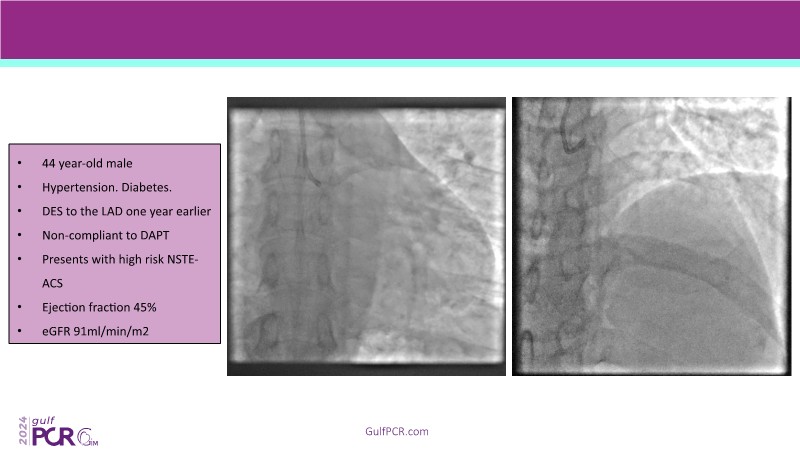

Explore cutting-edge strategies for optimizing drug-coated balloon (DCB) procedures in this session. Uncover practical tips to improve outcomes, review key indications, and examine international consensus on DCB use. Case presentations and expert discussions offer insights to refine your approach.

- To learn the tips and tricks to improve the result with drug coated balloon strategy

- To learn about the indications for drug coated balloon strategy